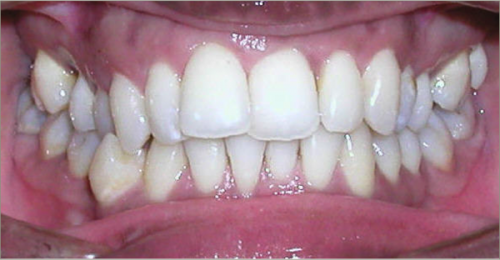

32 year old female:

Diagnosis:

- Previously lost upper first molars

- Severe lower arch crowding

- Midline discrepancy

- Narrow upper arch form

Treatment:

- Extraction of lower right first bicuspid

- Substitution of upper second molars for first molars

- Full fixed appliances

- 23 months